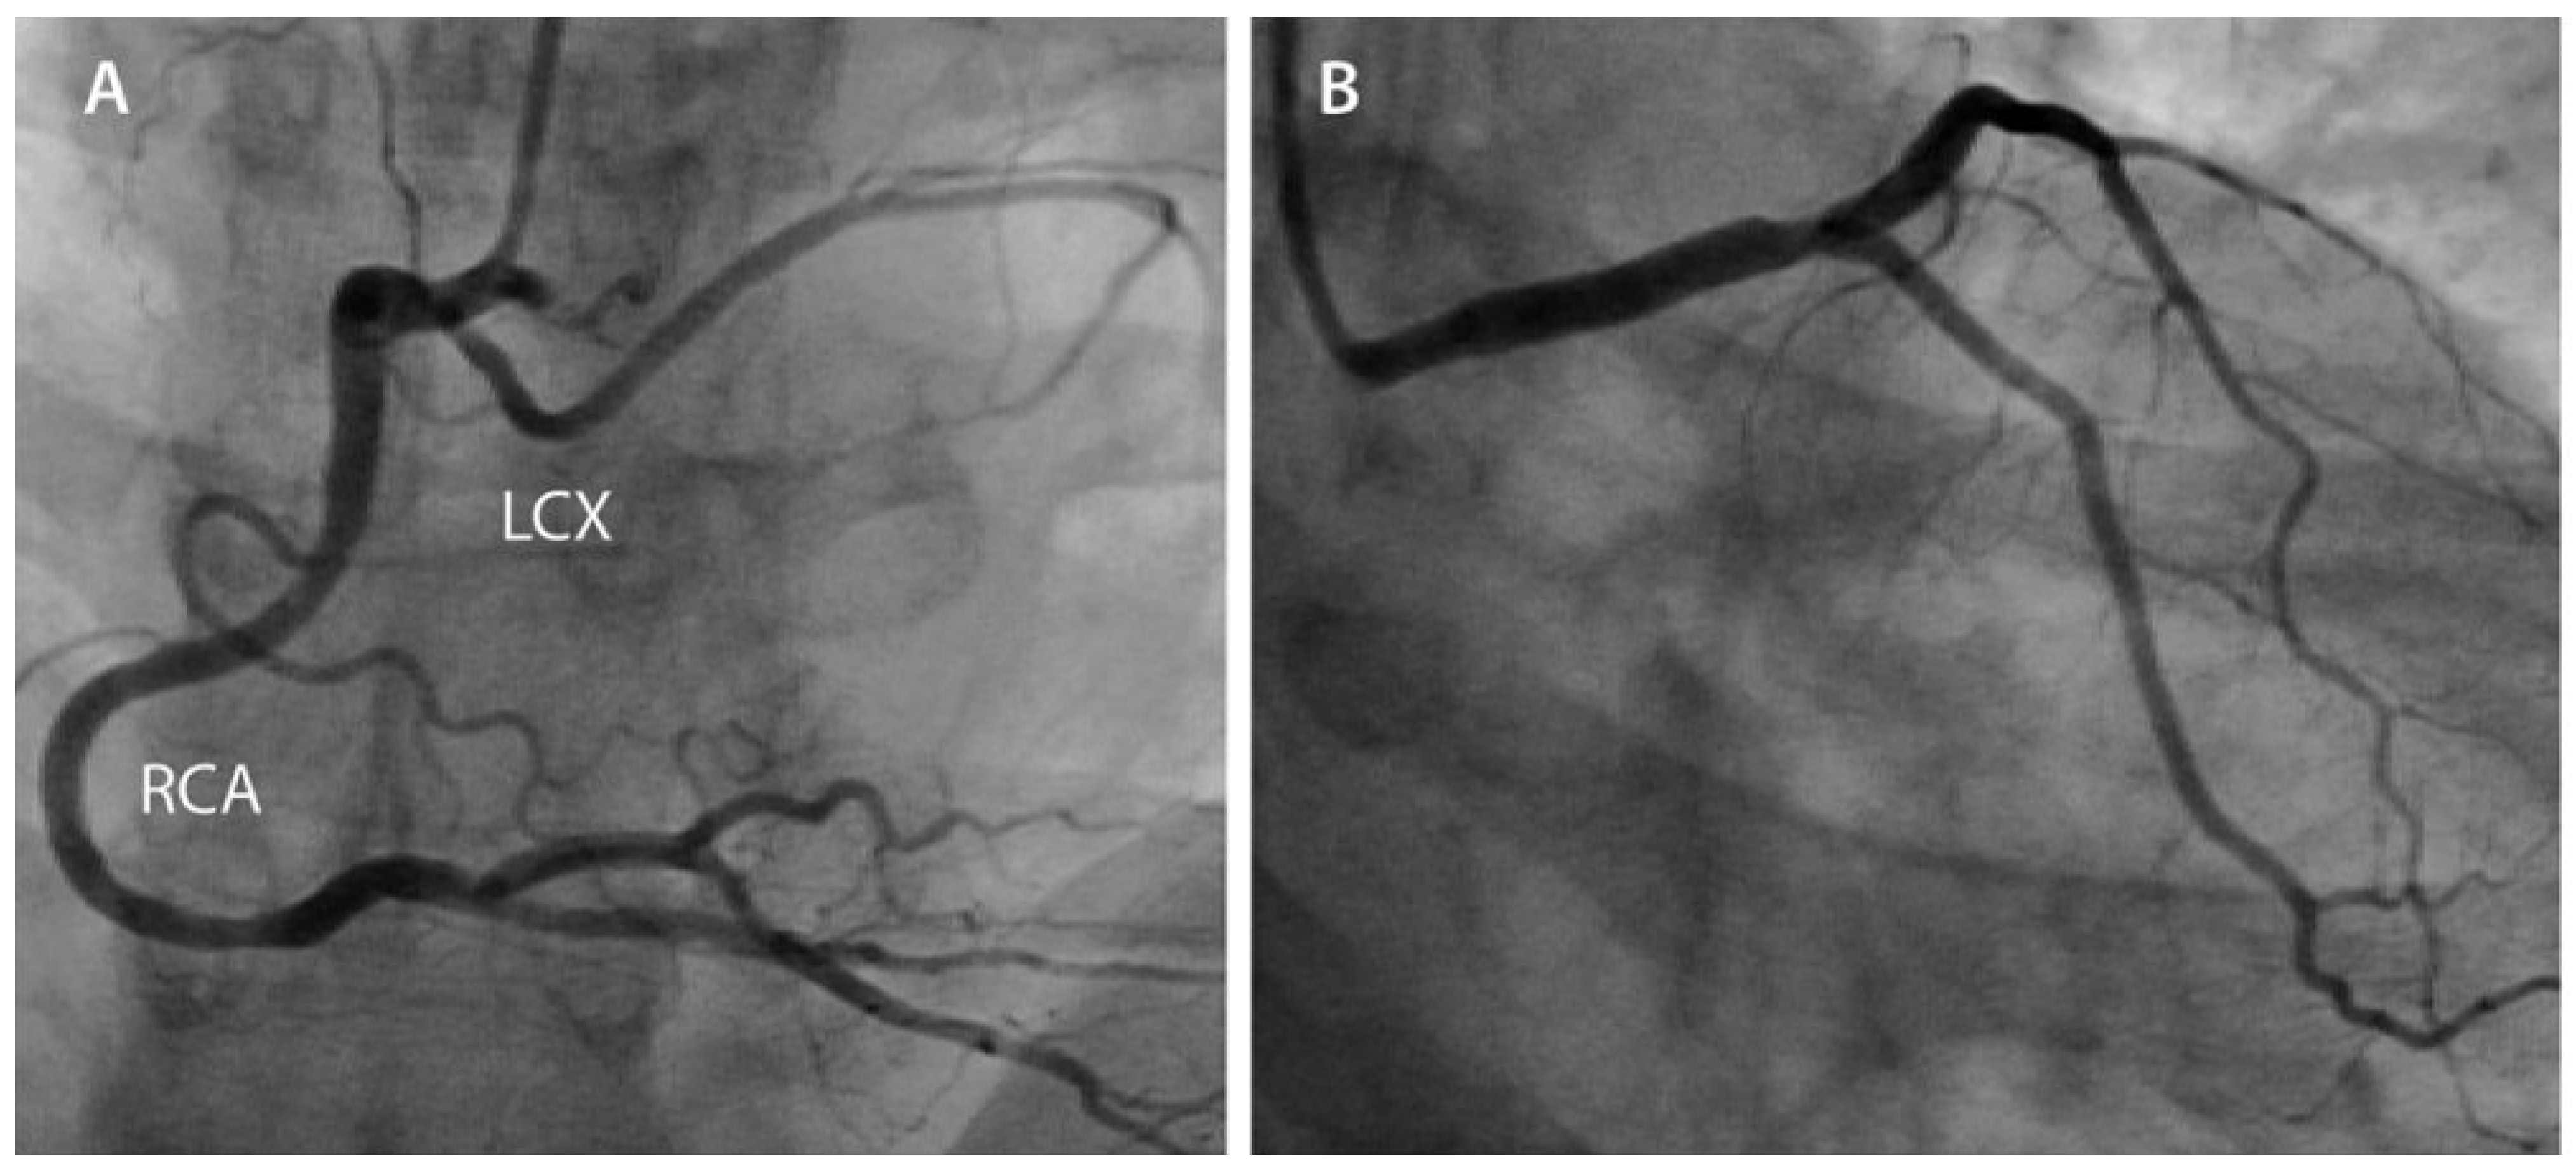

The right coronary artery (RCA) injection, performed thereafter, showed a normal dominant RCA with a partially aberrant left circumflex coronary artery (LCX), with the first OM arising from the left coronary tree (Figure 2A). At the end of the primary PCI, an intra-aortic balloon pump (IABP) was inserted through the right femoral sheath and kept there for 48 h. The maximal creatine kinase and troponin values were 4800 U/l and 110 µg/L, respectively. Left ventricular ejection fraction (LVEF) was moderately decreased (35%) at transthoracic echocardiography (TTE).

At 3 months, the LVEF was 40% on TTE assessment and the control coronary angiography at 9 months did not show any significant re-stenosis (Figure 2B) in the LMS stent. Under 40 mg atorvastatin and lifestyle modification, LDL cholesterol decreased from 5.6 to 1.3 mmol/L, and at the one-year follow-up the patient was free of symptoms.

Figure 2. (A) Cranial antero–posterior projection showing the right dominant coronary artery (RCA) and the aberrant left circumflex coronary artery (LCX). (B) One-year angiographic follow-up (right anterior oblique and caudal projection).